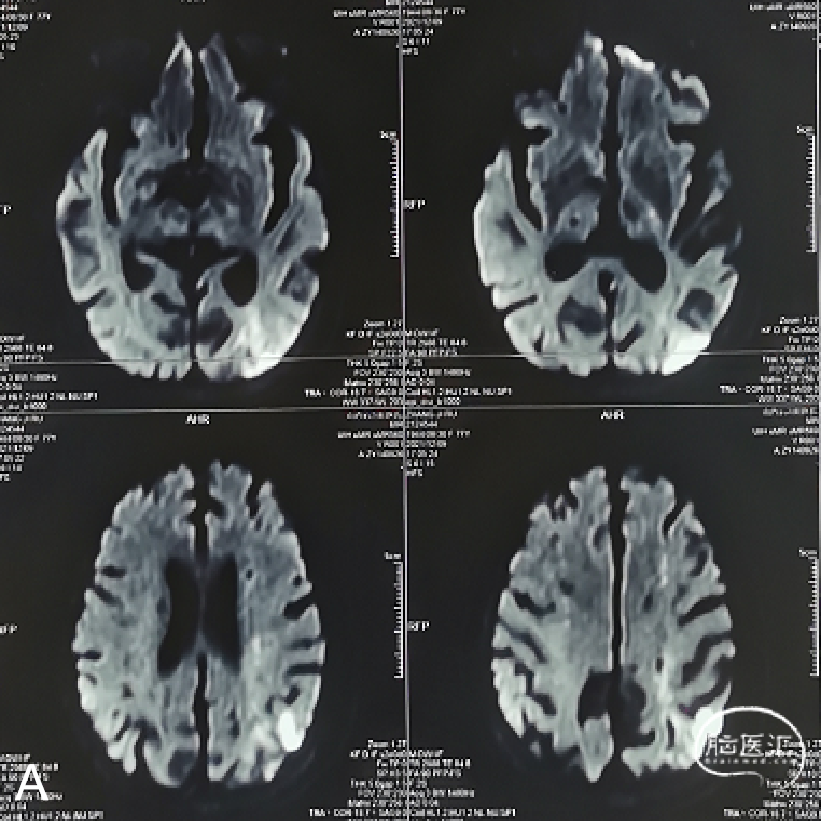

术前影像学检查结果

外院行头颅核磁示:左侧额顶枕叶急性脑梗死;颅内多发陈旧性脑梗死。

外院行脑血管造影示:左侧颈内动脉眼动脉段重度狭窄。